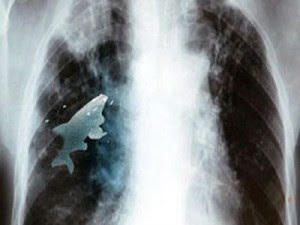

Οι γιατροί χειρούργησαν ένα 12χρονο αγόρι για να αφαιρέσουν από τον πνεύμονά του ένα ψάρι, ζωντανό!

Σύμφωνα με την εφημερίδα Sun, o μικρός Ανίλ Μπαρέλα (Anil Barela) κατάπιε ένα γεμάτο λέπια ψάρι 9 εκατοστών ενώ έπαιζε σε έναν ποταμό στην περιοχή Khargone.

Οι νεαροί Ινδοί συνηθίζουν να καταπίνουν ζωντανά ψάρια για πλάκα. Το συγκεκριμένο ψάρι όμως, με ένα απίθανο τρόπο, κατέληξε στον πνεύμονα του 12χρονου αντί για το στομάχι του!

Οι γιατροί τον έβαλαν επειγόντως στο χειρουργείο καθώς ο νεαρός δεν μπορούσε να αναπνεύσει.

Το ψάρι ήταν ζωντανό μέχρι που το αφαιρέσαμε, γεγονός που περιόριζε τη λειτουργία των πνευμόνων του αγοριού και του στερούσε οξυγόνο , δήλωσε ο ένας εκ των ιατρών.